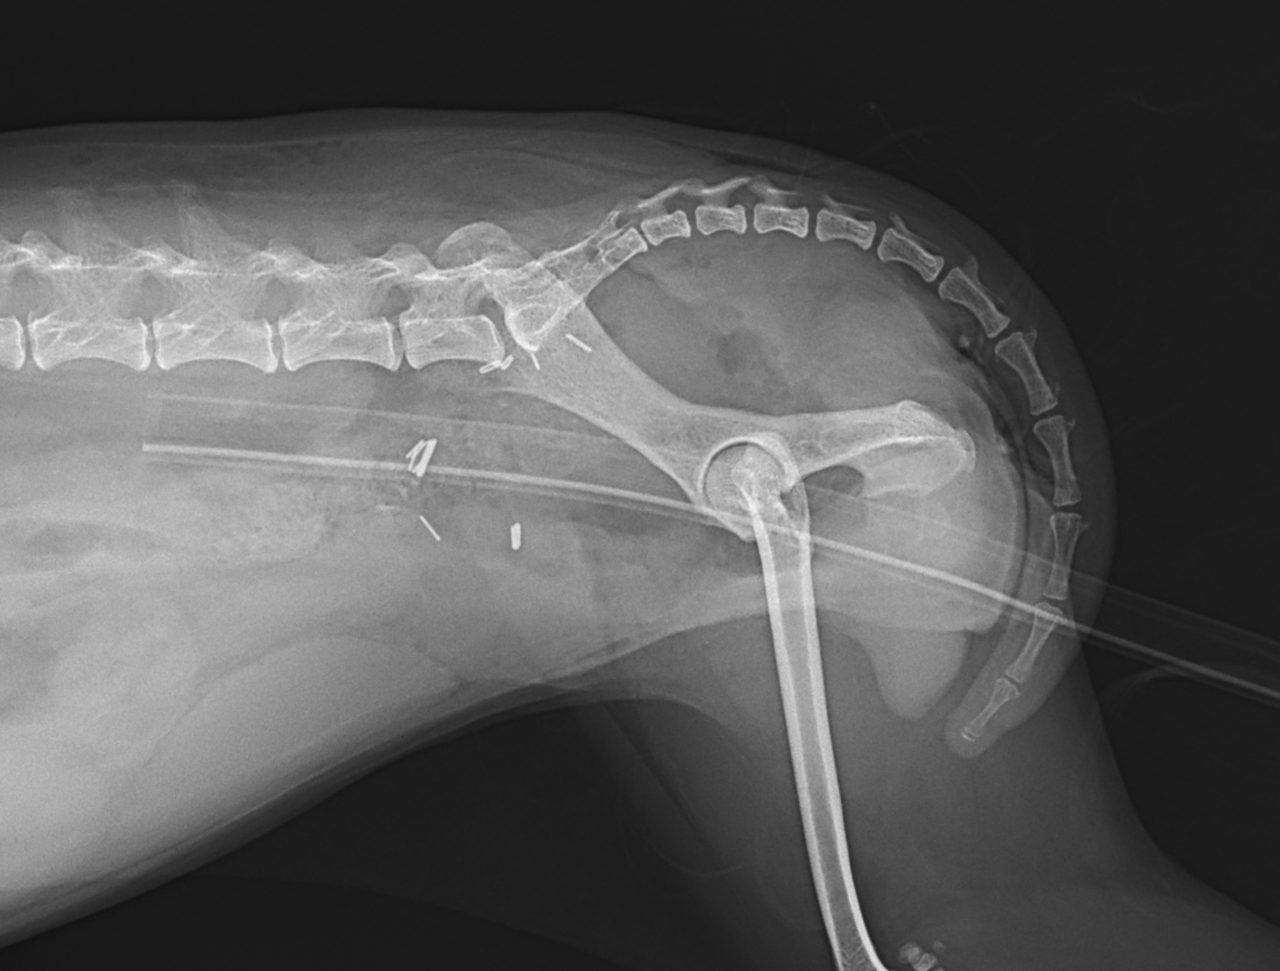

鎮痛剤で跛行が改善しないワンコの精査依頼がありました。CTでは股関節(主に腸骨)に骨融解像が確認されました。細胞診では悪性腫瘍と暫定診断が行われました。除痛のため半側骨盤切除で対応しました。後肢を失うことは大変辛いことですが、ワンコは痛みがなくなり快適に過ごせているそうです。一見、整形外科に見えても高齢犬には腫瘍が隠れていることがあるのでCTによる精査は大変有効です。